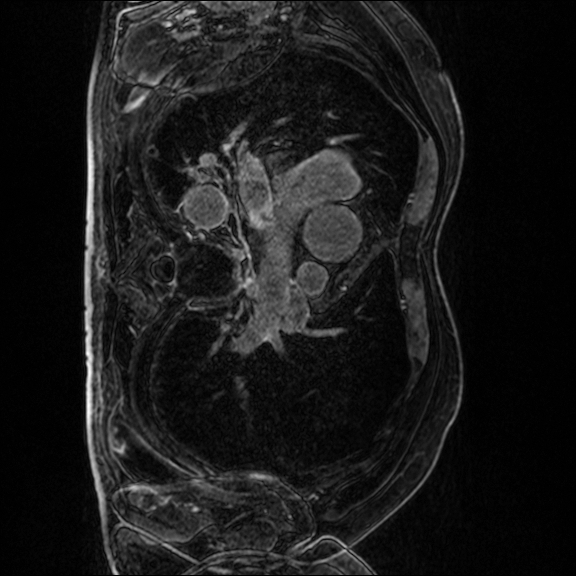

Late gadolinium enhancement magnetic resonance imaging (LGE-MRI) is typically used to provide quantitative information on atrial scars [25]. In this measurement, location and size in the left atrium (LA) indicate pathology (i.e., LA scars) and progression of atrial fibrillation [12].

Nowadays, deep learning models have been widely used to segment LA cavities and quantify LA scars from LGE-MRIs [3] to help radiologists with initial screening for quick pathology detection. Meanwhile, LGE-MRIs are often collected by multiple scanners and possibly in low imaging quality. Each of them produces inconsistent domain information [14], including different contrast and spatial resolutions. (1) Promoting the generalization of a segmentation model against domain inconsistency becomes another challenge.

The LAScarQS dataset includes two tasks: 1). LA and LA Scar segmentation (task 1), and 2). LA Segmentation across scanners (task 2). The first task contains 60 3D LGE-MRIs with labels containing LAs and LA scars, while the second consists of 130 3D LGE-MRIs from multiple medical centers with labels containing only LAs [12].